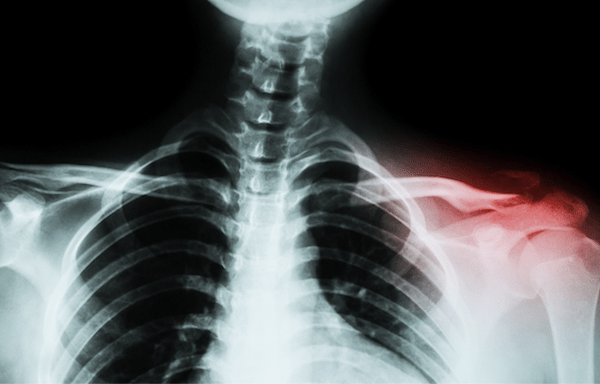

Amed®鎖骨プレーティングシステム外科技術 上面幹骨部鎖骨プレートの外科技術 William B Geissler, mD 1 鎖骨骨幹部骨折のX線撮影オプション X線評価は、肩鎖 (AC) 関節、胸鎖 (SC) 関節およ び烏口鎖骨 (CC) 靭帯を評価するために前後方向 (AP) 画像で開始します。1717 · 骨折での入院期間や手術で入れたプレートやボルトは抜く? 骨折はスポーツを愛する方なら避けられない怪我で、状況によりけりですが手術を行うこともあります。 もし手術となった場合、その時間や費用およびリハビリや術後の痛みなど気になるところは多くあるでしょう。About Press Copyright Contact us Creators Advertise Developers Terms Privacy Policy & Safety How works Test new features Press Copyright Contact us Creators